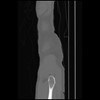

7 CUERPO,CE,Sagittal,3.000,CUERPO,Sagittal,